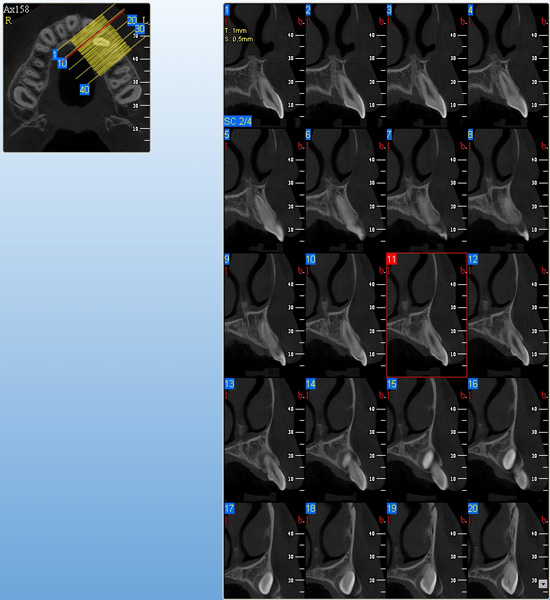

NewTom Implant Planing

Jedná se o plánovací program, který využívá dat získaných při vyšetření pomocí přístroje New Tom. Tento program umožňuje tříprostorovou počítačovou simulaci při plánování pozic implantátů.

Součástí programu je i databáze, ve které mohou být uloženy všechny typy implantátů od všech výrobců, včetně jejich délek, průměrů i tvarů.

Lékař si vytvoří všechny typy zobrazení potřebných pro naplánování – tedy 2D snímky (panoramatický), příčné řezy i 3D model.

Vidí zde i důležité anatomické útvary – čelistní dutinu, průběh nervu atd. Po proměření množství kosti – šířky i výšky vybere z databáze vhodný typ implantátu a umístí ho do požadované lokality.

Ihned vidí jeho pozici ve všech 3 rovinách a na všech snímcích i 3D modelu. Může upravovat podle potřeby jeho pozici, sklon atd.

Všechny vybrané a správně umístěné simulované implantáty se ukládají do „počítačové karty“ pacienta s jejich pozicí, délkou, průměrem, typem i sklonem.

Lékař i pacient tedy ještě před vlastní operací vidí, jak by mělo ošetření probíhat a vypadat.